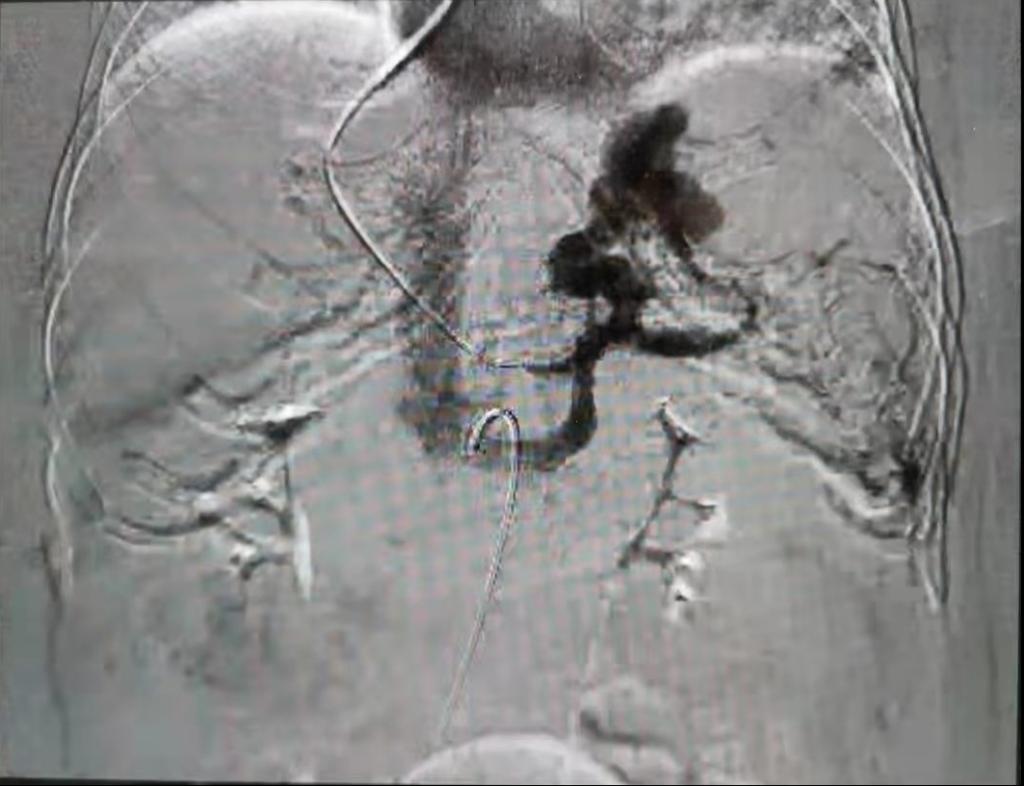

为预防患者再次出血,解决门静脉高压,消化内科医护人员经讨论后决定行TIPS术治疗。8月10日,在院领导及介入科、心内科、普外科等相关科室大力支持下,消化内科王宇晖主任、赵新功副主任医师、王亚茹护士长、常月红主管护师等组成的手术团队,在介入科顺利完成了间接门静脉造影术、TIPS支架置入术、胃冠状静脉栓塞术及脾胃肾分流道封堵术。术后患者恢复良好,第二天即可下地活动。术后复查TIPS支架通畅,第四天患者出院。

TIPS手术(经颈内静脉肝内门体静脉分流术)是治疗肝硬化失代偿期食管胃底静脉曲张出血的一把利器,是解决肝硬化失代偿期上消化道大出血最直接、有效的治疗手段。该手术可以解决患者反复出血、难治性腹水及根本上解决门脉高压问题,但因手术难度大,技术要求高,目前在我国仅少数医院开展,在陕西省能够开展的医院屈指可数。消化内科TIPS手术的开展,为渭南市肝硬化失代偿期患者带来更多生的希望,也将医院消化介入诊疗技术带入全省先进行列。